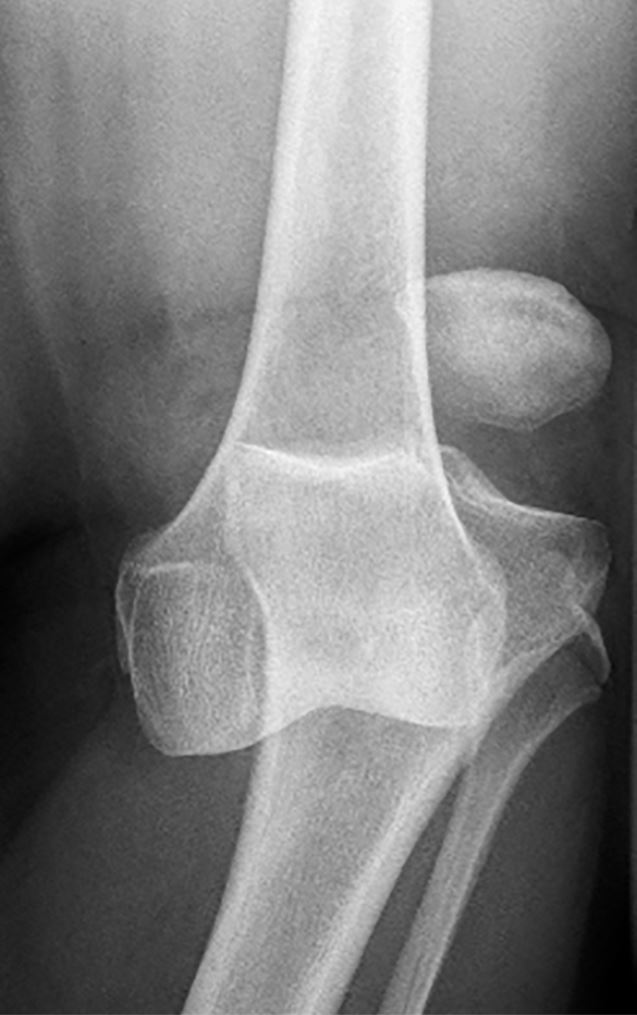

Tatort einsamer Wald: Ende Juni 2020 geht eine 50-jährige Frau mit ihren zwei Hunden in einem einsamen Wald spazieren. Als sie unvermittelt von Wespen - die sich offensichtlich durch ihr Erscheinen gestört fühlten - attackiert wurde, geriet sie ins Stolpern, stürzte und verdrehte sich das Kniegelenk. Dabei zog sie sich eine üble, ausgedehnte Verletzung ihres linken Kniegelenkes zu, mit Luxation des Kniegelenkes (Abb. 1), Ruptur des vorderen und hinteren Kreuzbandes, Läsion des Innenbandes, Bruch des Fibulaköpfchens, Fissur des Tibiaplateaus sowie eine Ruptur des medialen und lateralen Retinakulums.

Abb. 1: Kniegelenksluxation

© Prof. Willinek, Krankenhaus der Barmherzigen Brüder Trier